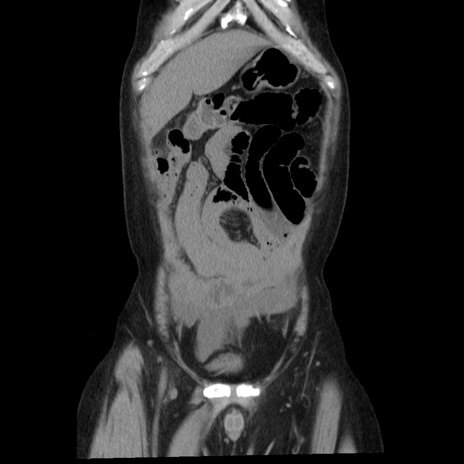

症例29(冠状断像)

【症例】40歳代男性

【現病歴】2日前から胃痛あり。徐々に周期的な激痛に変化した。本日になっても激痛があるため受診。

【身体所見】意識清明、BT 38-39℃台あり、腹部:膨満、やや硬、右下腹部に圧痛あり。

【データ】WBC 8500、CRP 23.26